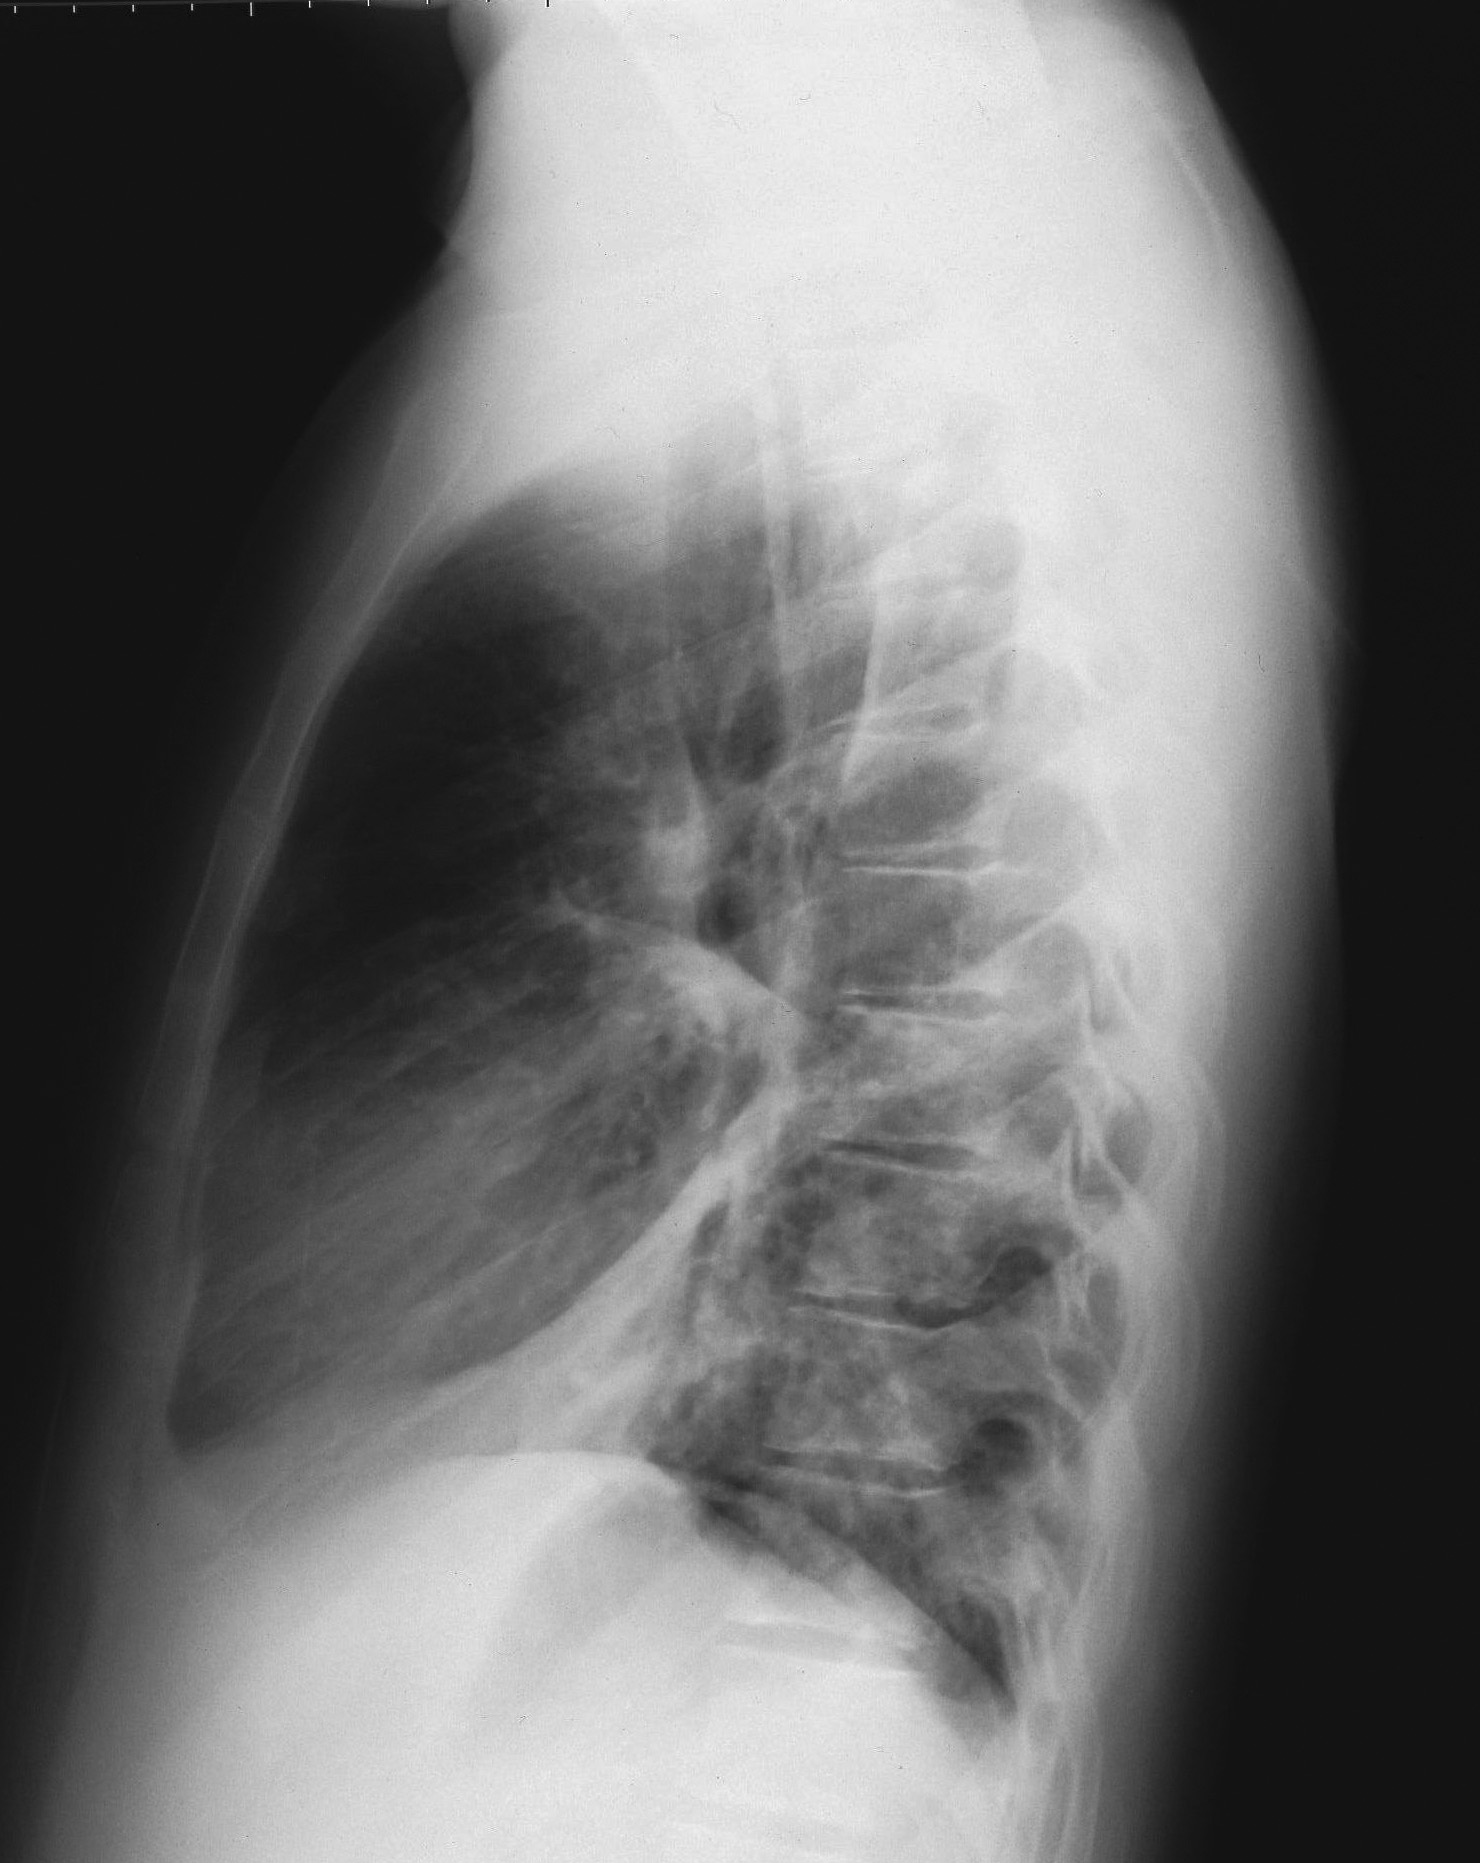

Nel complesso, cinque pazienti hanno presentato gastro-enterite con severa disidratazione, quattro bronco-polmonite con crisi dispnoiche, due bronco-ostruzione con crisi di cianosi, uno impetiginizzazione delle lesioni cutanee e, infine, un paziente congiuntivite purulenta. I pazienti italiani hanno presentato una maggiore percentuale di complicanze rispetto ai pazienti rom (Figura 2). Tra i pazienti italiani, due hanno presentato gastro-enterite mentre tre hanno sviluppato una broncopolmonite, confermata dalla radiografia del torace (Figura 3). Il bambino di un mese � stato trattato con immunoglobuline e.v. Nessun paziente ha presentato complicanze neurologiche.

Figura 3a. |

Figura 3b. |

Figura 3. Radiogramma del torace in proiezione antero-posteriore (a) e latero-laterale (b) in un paziente italiano di 15.3 anni. � evidente una polmonite interstiziale bilaterale, pi� accentuata a dx, con obliterazione dello spazio retrocardiaco, diagnosticata dopo 2 giorni dalla comparsa dell'esantema.